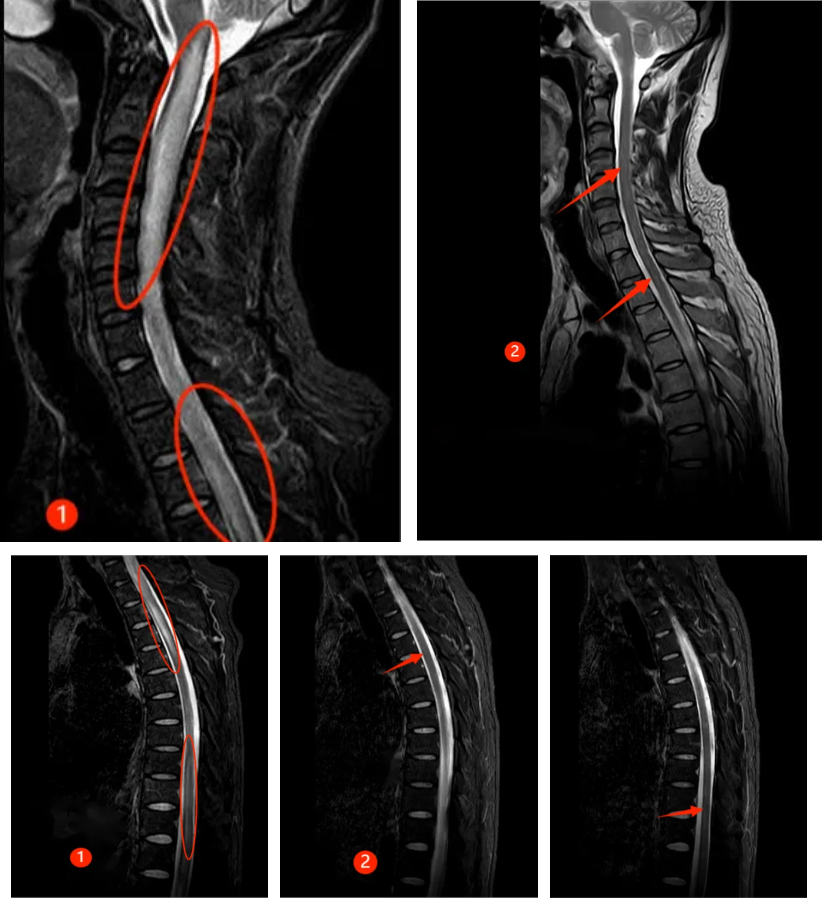

半年前,30 来岁的谭先生突然出现颈肩部疼痛不适及肢体麻木,此后短短数天迅速出现四肢瘫痪及大小便失禁,生活不能自理。正值风华正茂的年纪,谭先生一时无法接受,心急如焚的父母带着吓坏了的谭先生来郑州大学第五附属医院就诊,入住神经内科二病区。入科时患者已四肢全瘫,紧急完善相关检查,发现患者脑干、颈髓、胸髓、腰髓广泛病变(见图①),随后完善腰穿及相关抗体检查,最终确诊为 MOGAD。

经过及时的免疫治疗,患者病情逐渐好转,出院时患者已能下床行走,再次拾起对生活的信心,复查磁共振,患者脑干、颈髓、胸髓、腰髓的病变已明显好转(见下图②)。半年后随访,患者已恢复正常的生活,预后很好。